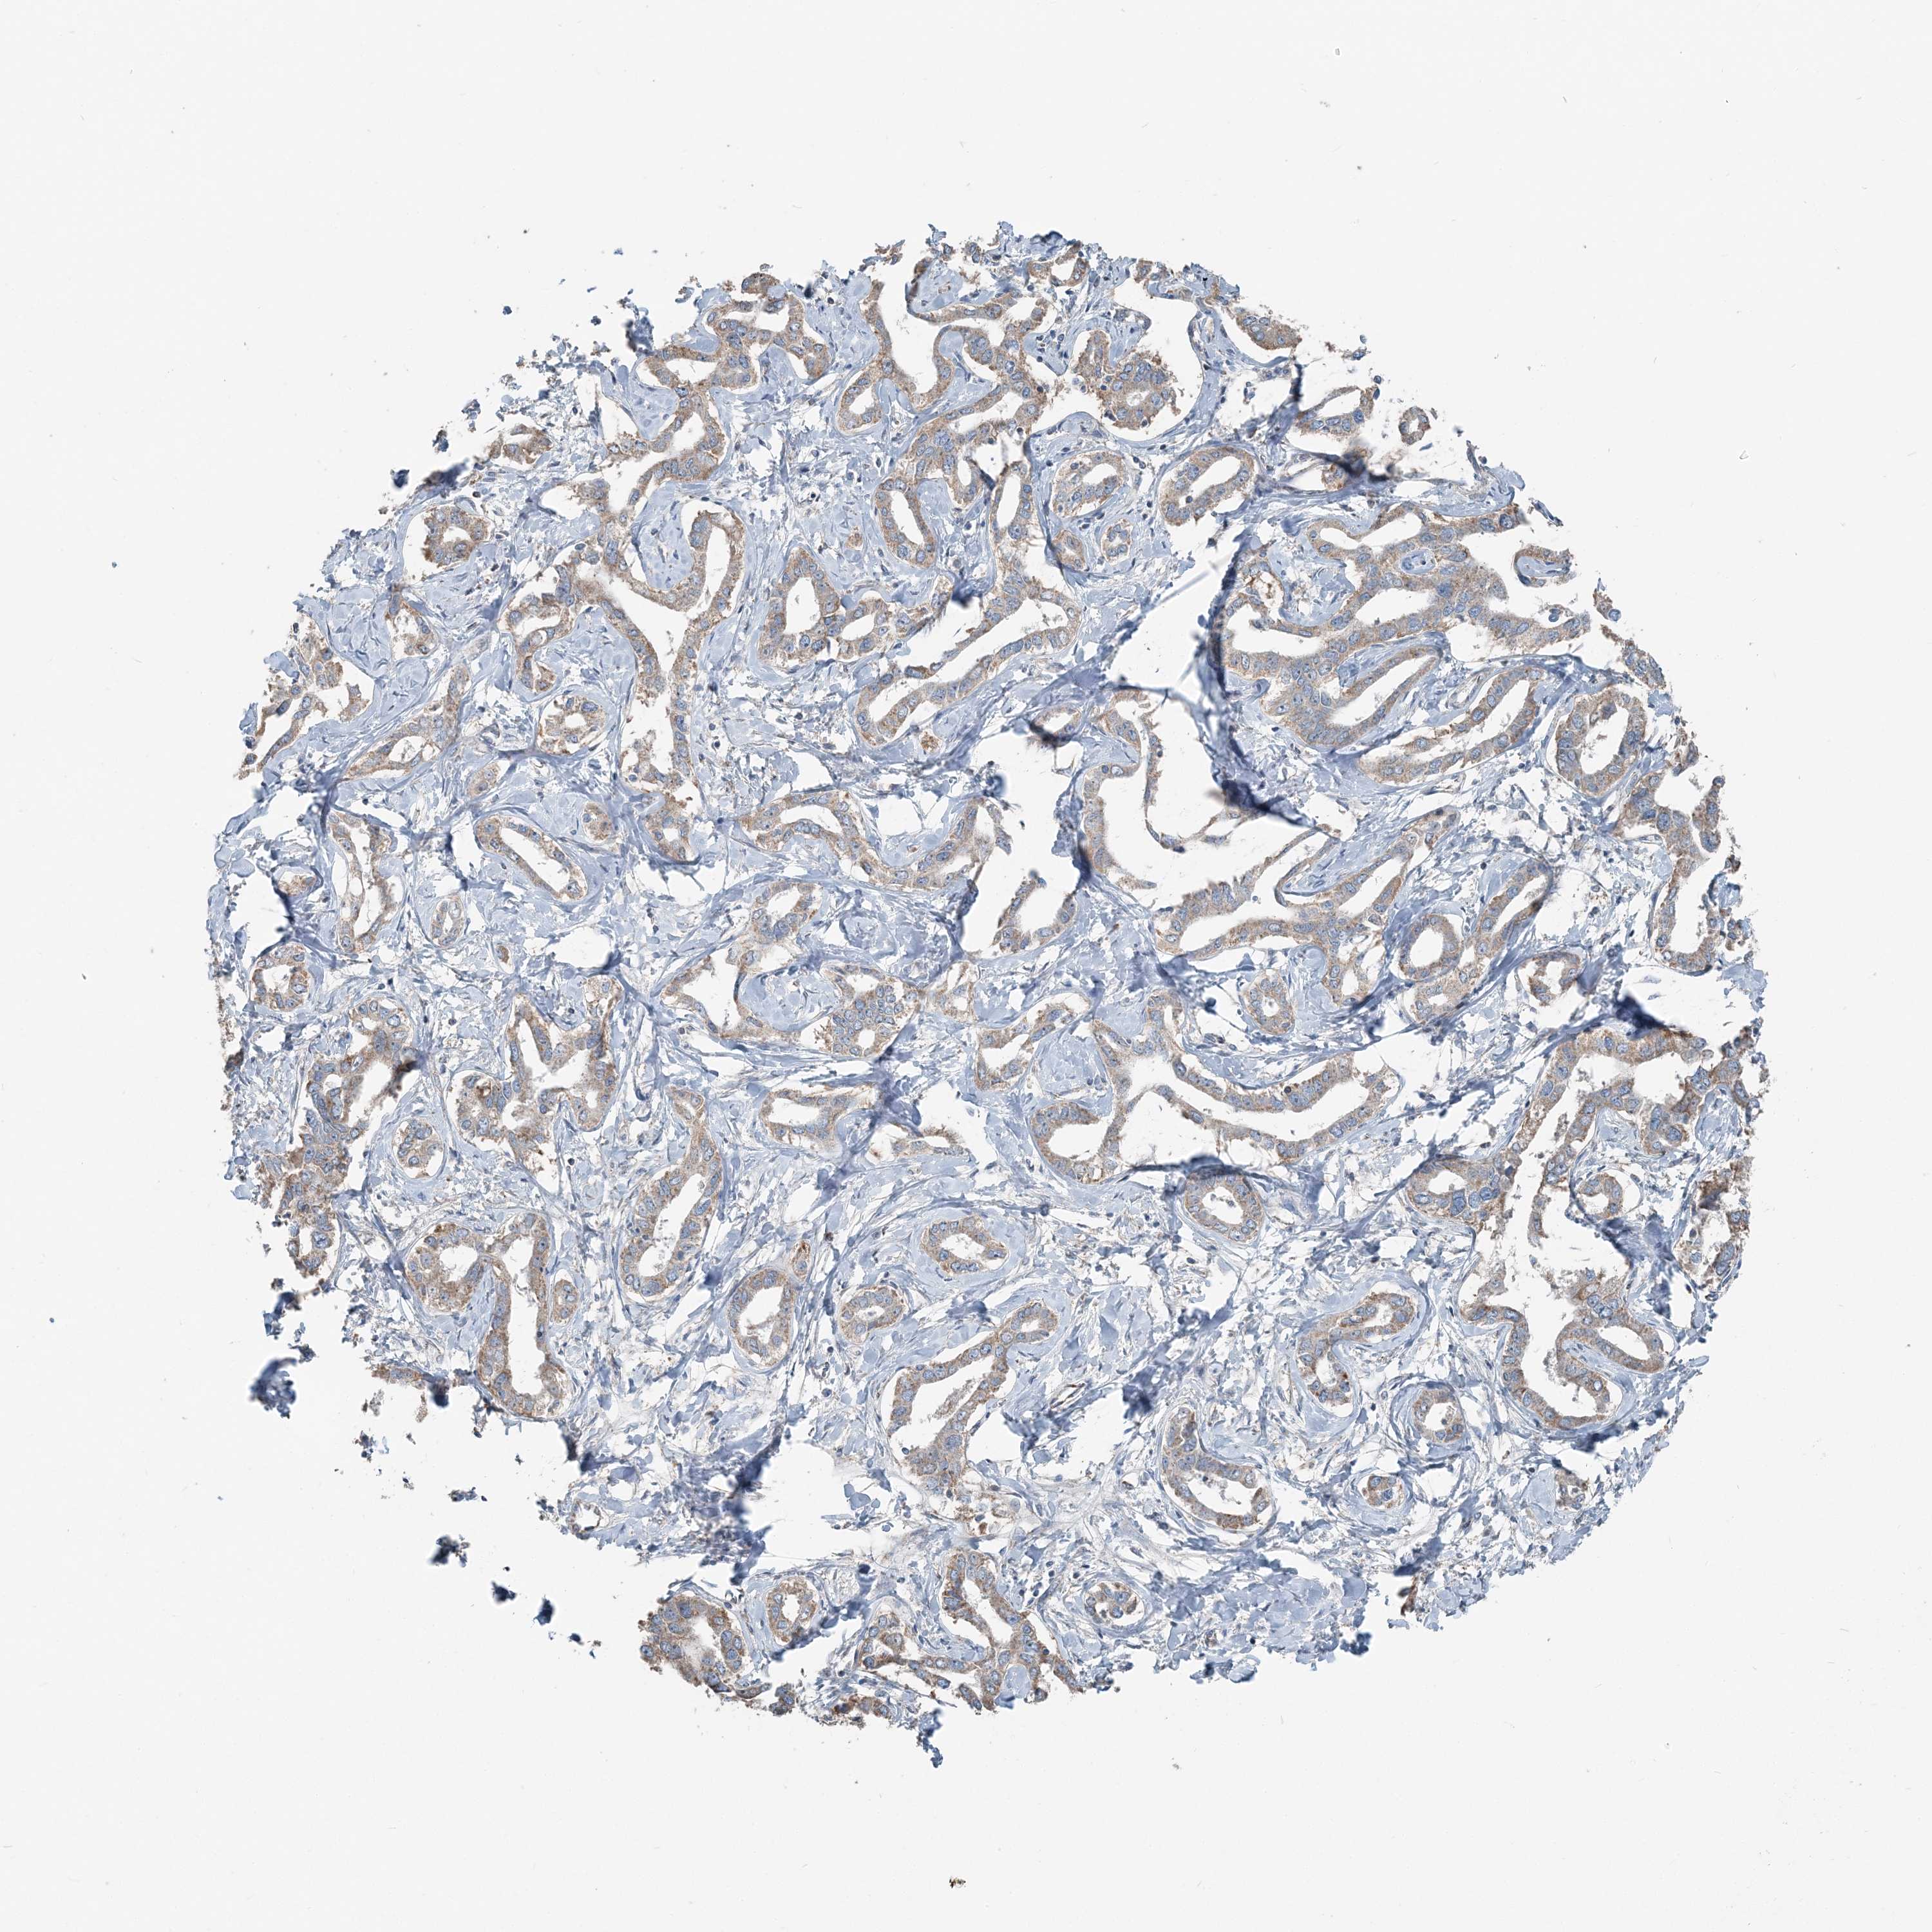

LIVER CANCER - Protein expressioni

A mouse-over function shows sample information and annotation data. Click on an image to view it in a full screen mode. Samples can be filtered based on level of antibody staining by selecting one or several of the following categories: high, medium, low and not detected. The assay and annotation is described here.

Note that samples used for immunohistochemistry by the Human Protein Atlas do not correspond to samples in the TCGA dataset.

Antibody stainingi

Antibody staining in the annotated cell types in the current human tissue is reported as not detected, low, medium, or high, based on conventional immunohistochemistry profiling in selected tissues. This score is based on the combination of the staining intensity and fraction of stained cells.

Each image is clickable and will lead to virtual microscopy that enables deeper exploration of all samples and also displays staining intensity scores, fraction scores and subcellular localization as well as patient and tissue information for each sample.

Antibody HPA036683

Antibody HPA036684

Staining

High

Medium

Low

Not detected

Intensity

Strong

Moderate

Weak

Negative

Quantity

>75%

75%-25%

<25%

None

Location

Nuclear

Cytoplasmic/membranous

Cytoplasmic/membranous,nuclear

Cholangiocarcinoma

Carcinoma, Hepatocellular, NOS